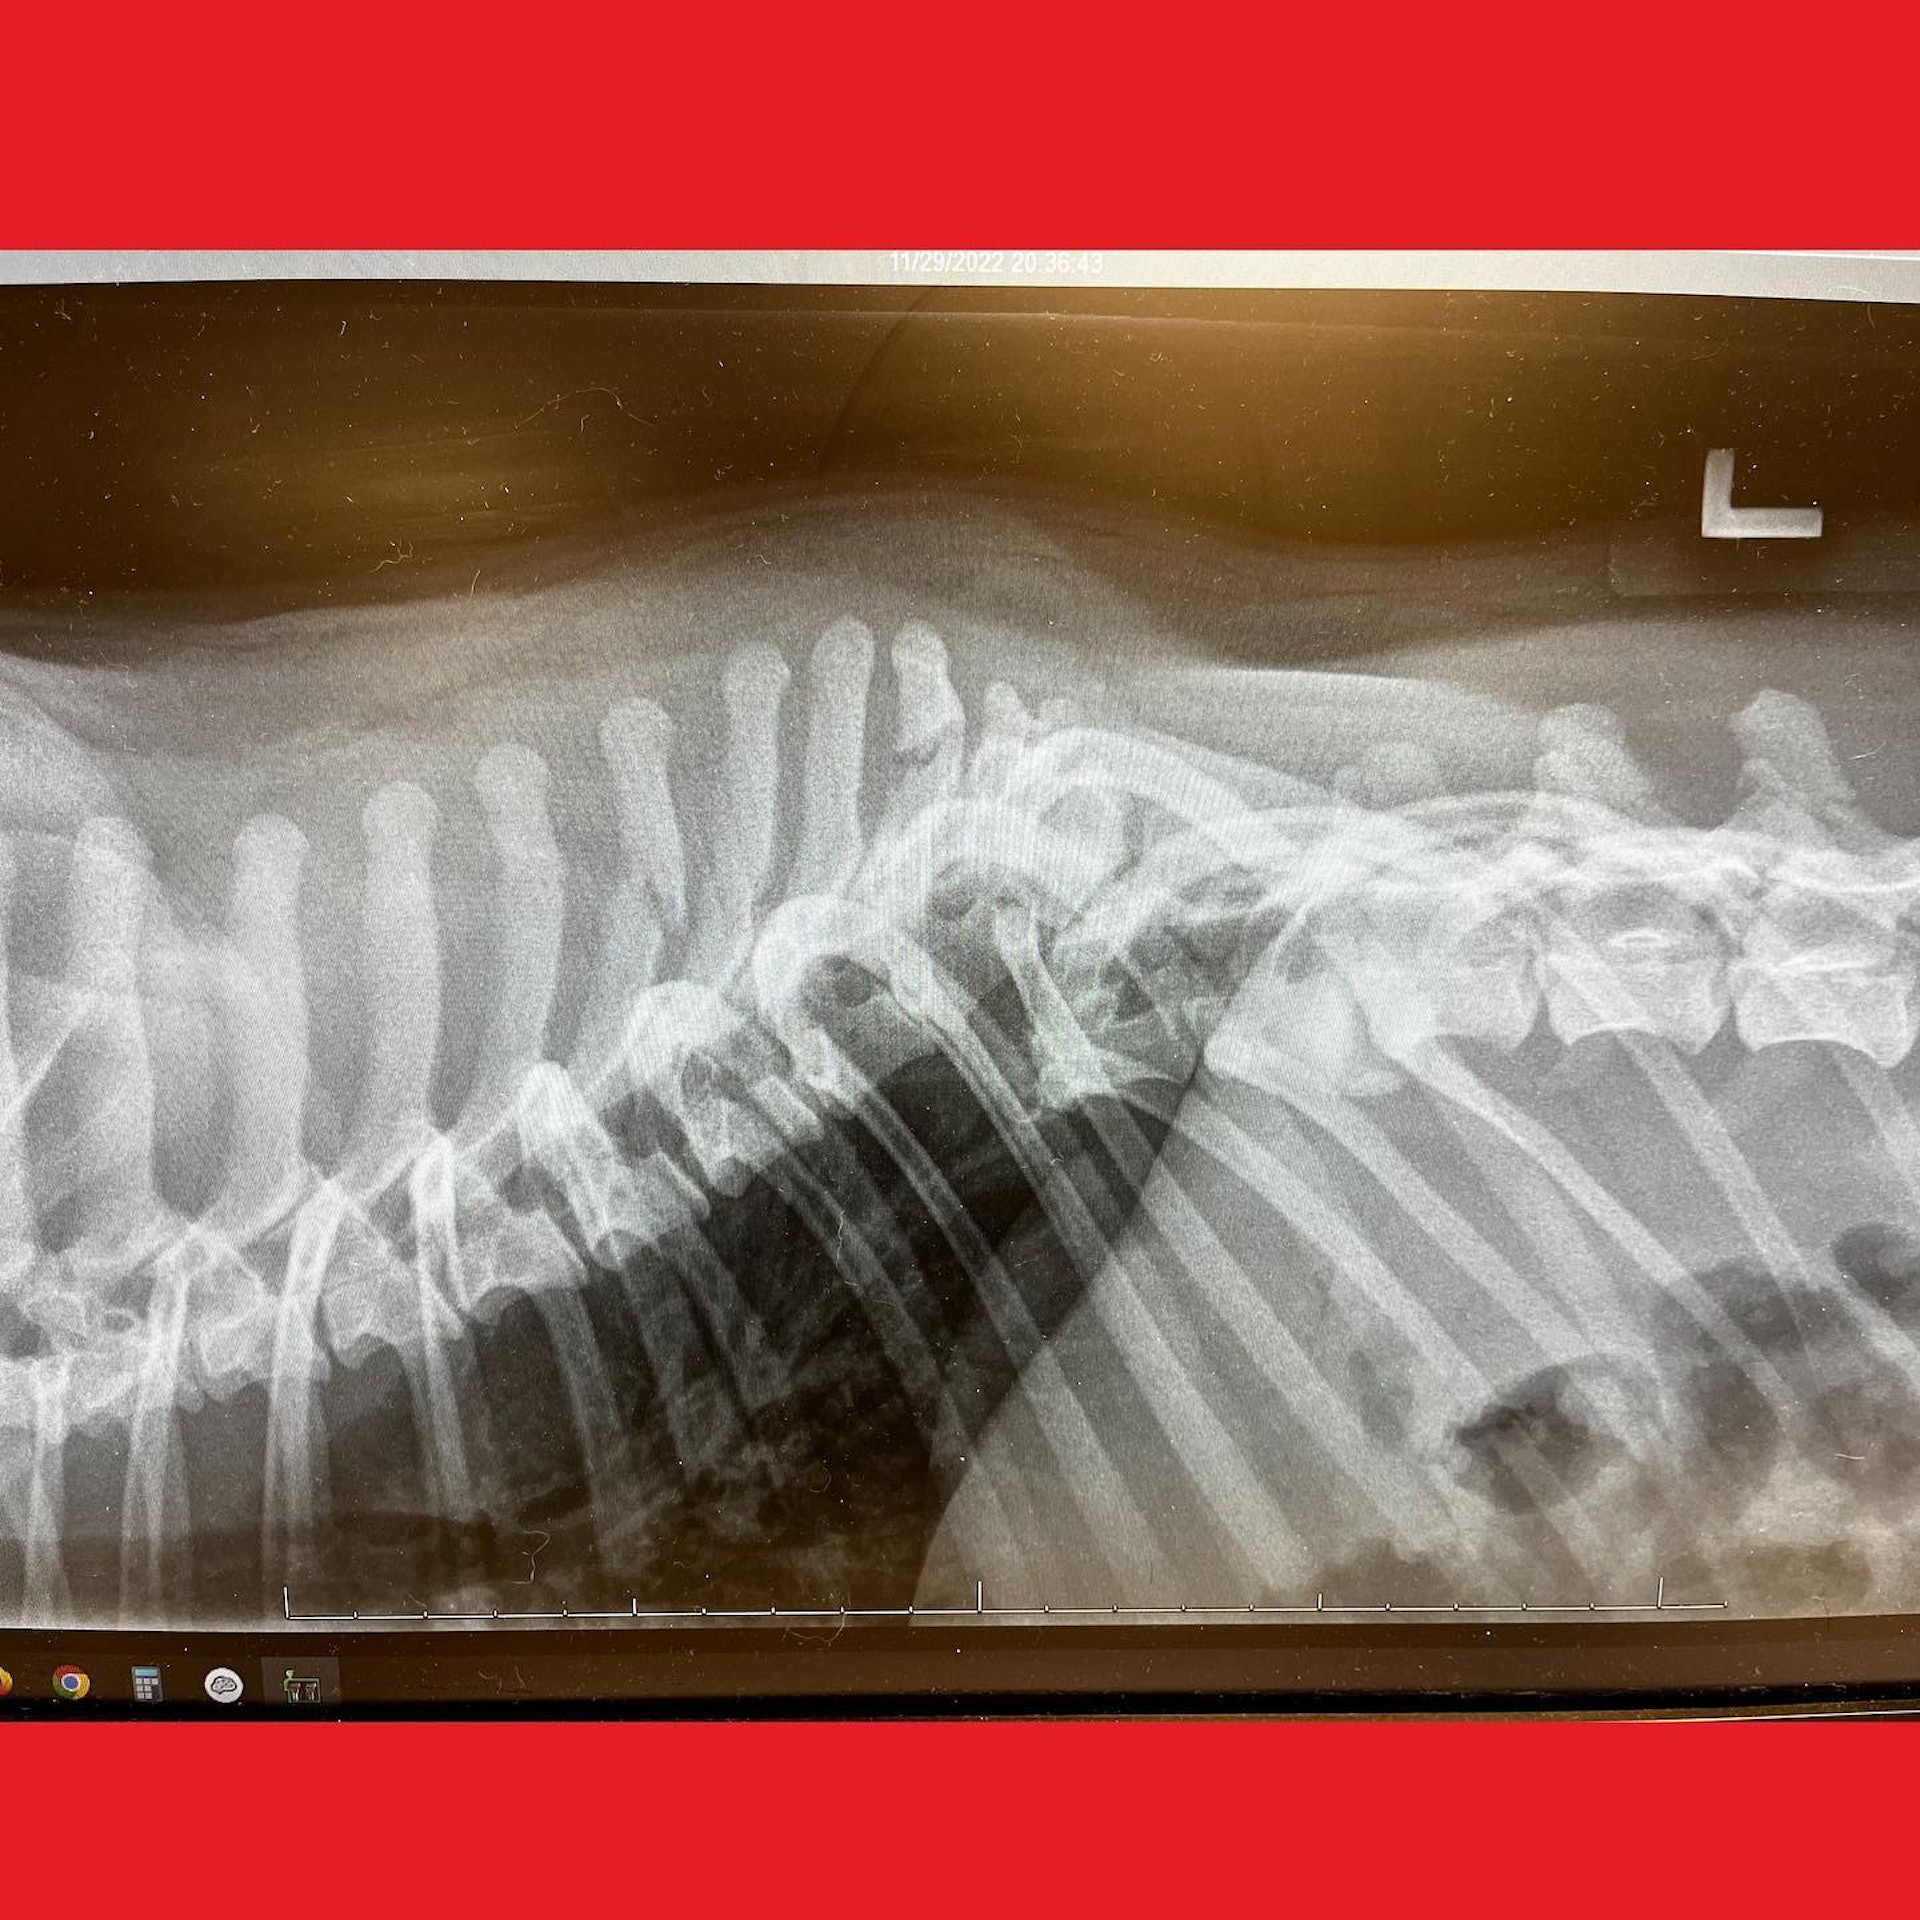

He had deep, inflamed scrapes all over his body and broken teeth from frantically trying to survive. But the X-rays revealed the most devastating news of all. His spinal cord was completely severed. It was the worst spinal fracture the veterinary team had ever seen.